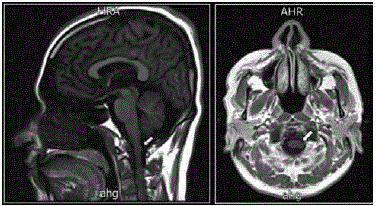

Deworming was completed after 26 days of admission in the service. Although the evolution of the patient indicated improvement, headaches did not diminish. Finally, a HMRI was taken, showing, on the one hand, two hyperintense punctiform images of corticosubcortical location in the left frontal region and towards the ipsilateral Sylvian fissure compatible with residual calcifications, and, on the other, a rounded cystic image, with intermediate signal intensity and hyperintense with walls that enhance the lateral contrast and apparent contact with the medulla oblongata on the left side, which was about 6x3mm long (Figure 3).

The results of the studies concluded a cystic lesion adjacent to the medulla oblongata and enhancement of the walls that, in association with chambered images of multicystic appearance in the subarachnoid space of the posterior fossa and cortico-subcortical calcifications, lead to discard NCC (Figure 3). The patient progressed satisfactorily with complete improvement of the symptoms and was discharged without complications.